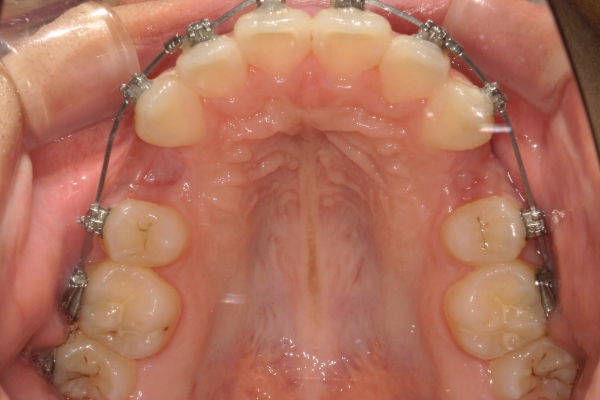

PROCESS

半年

上顎前歯が1 cm近く前方に出ており、叢生を改善しつつ前歯を大きく引っ込めるために上下顎小臼歯の抜歯が必要と診断しました。治療では奥歯の噛み合わせのズレも整え、治療後は前歯でも奥歯でも食べ物が噛みやすくなったと、患者さまに非常に満足していただけました。